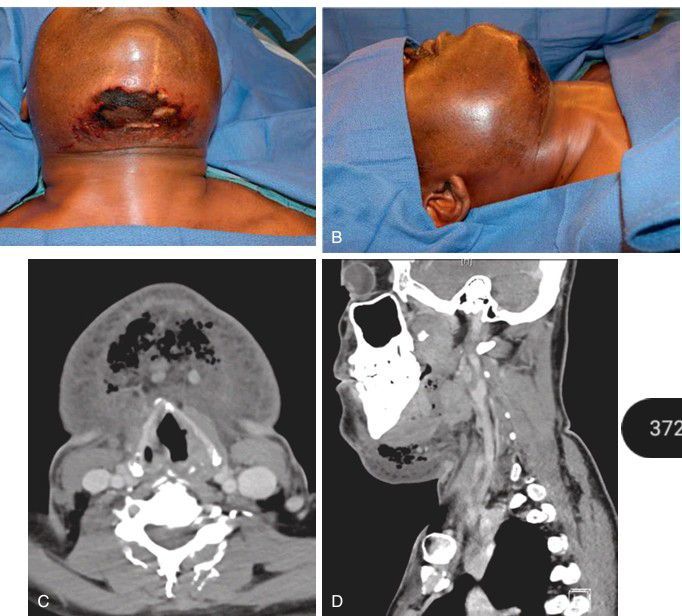

A–B) A patient who presented to the emergency department with bilateral chronic periapical odontogenic infections causing diffuse edema and overlying skin breakdown of the neck. (C–D) Computed tomography demonstrating destruction of the normal anatomic fascial planes of the neck.